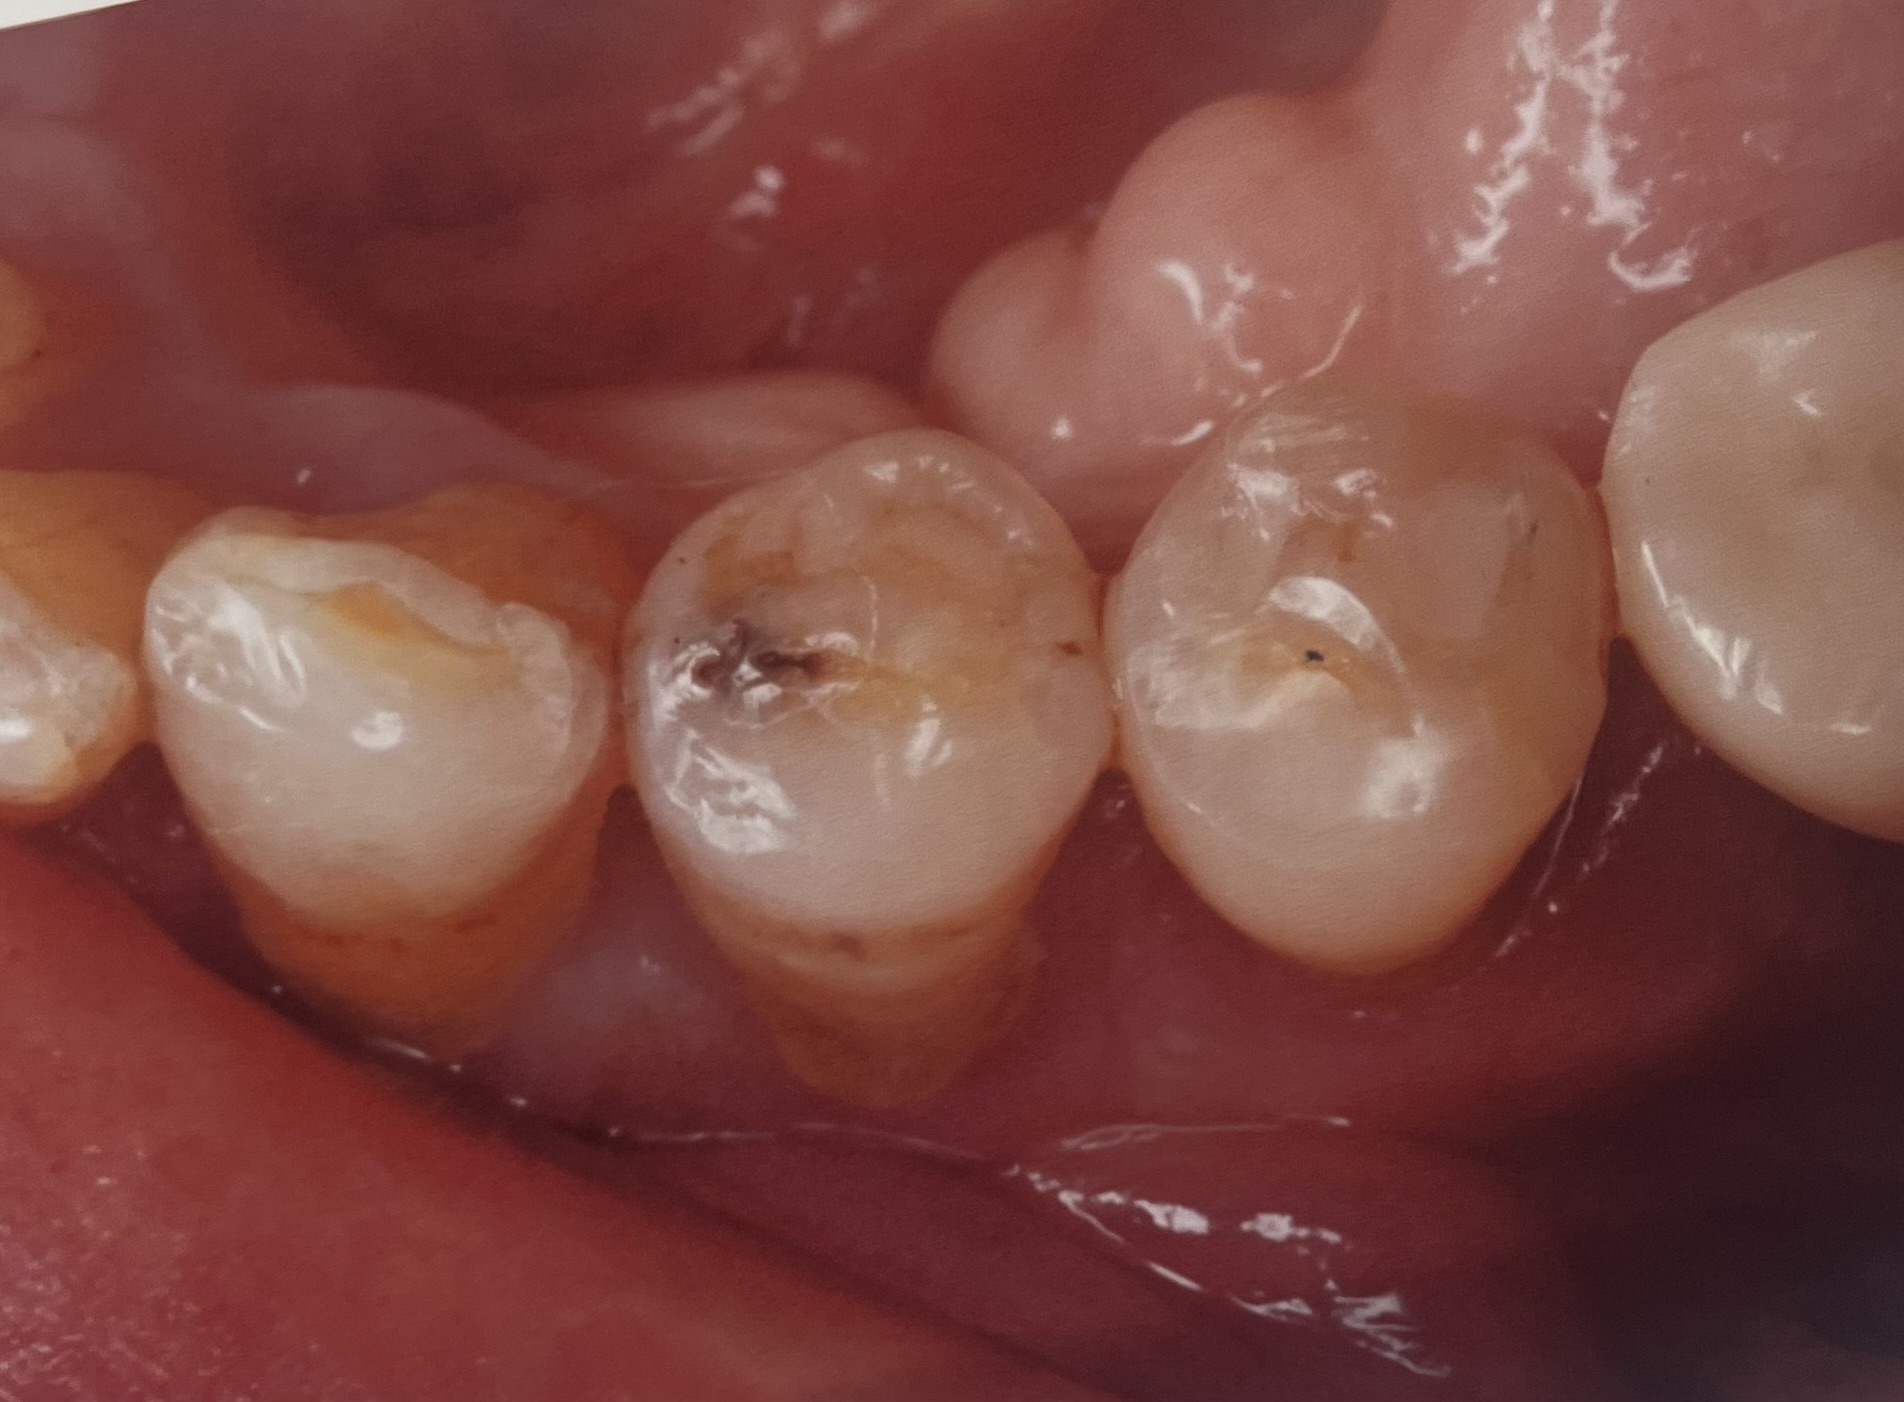

埼玉県志木市の佐藤デンタルクリニックです。今回は、部分的な銀歯を含む虫歯をぶぶんなセラミックで治療したものです。

しかし、銀歯治療には現代には即さない致命的な欠陥があります、特に今回あげた銀歯(アマルガム)と言われるおもにに昭和時代に行われた詰まる治療は、元々の治療が深いことが多く、神経まで到達してしまうことが多くほっておくと神経を取る治療になりやすい欠点があります、

また、アマルガムは物にもよりますが、水銀を含んでああることがあり、アレルギーの観点からも口の中に入れるのは良くないと現代では言われています、

ここには治療例を二つほど載せましたが、当院での治療数は、部分的なものだけで1500を超えています!そのなかで、銀歯のように外れたとかしみる、かけたなどの問題はほぼおきていません。

今回の治療は、エナミックという弾力があり、かけにくい噛みやすいセラミックを用いて行なっています、価格は、65000-80000円(税別)となります、虫歯の大きさなどによっては全体を覆うものも良いかと思いますが、歯の歯質を残したい方にはこの治療がおすすめです、